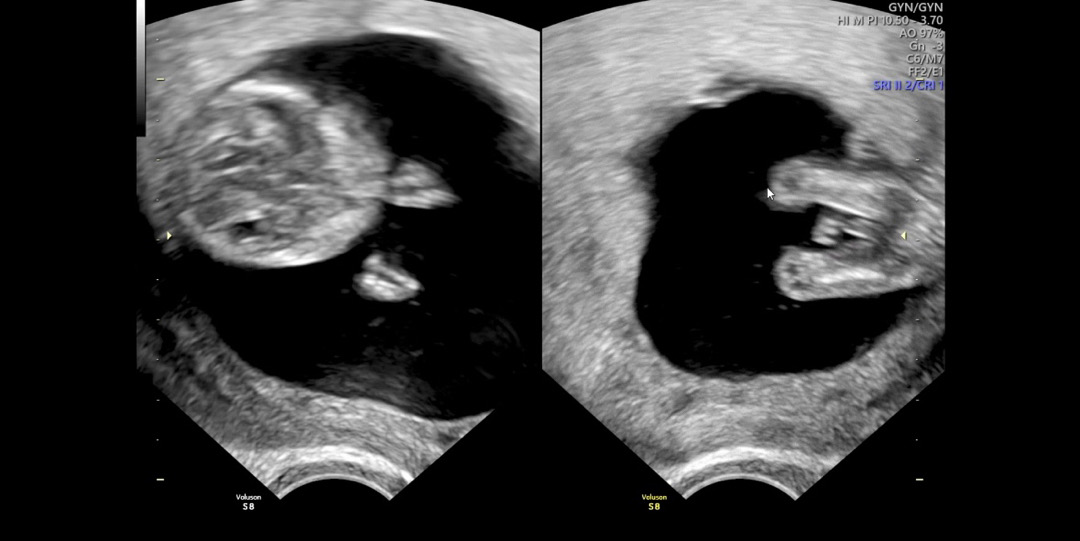

12주 3일에 본 다리사이에 이것은?!

다리 사이에 보이는 이것 아들일까요?? 12주 조금 지나서 보인건데 바뀔 가능성이 있을지 궁금하네요 ㅋㅋㅋ

ㅋㅋㅋㅋ 미사일 ㅋㅋㅋ선명하져

저희 첫째 아들 초음파사진이 딱 저랬어용!ㅋㅋㅋ

빼박 아들인가보네요 ㅋㅋ 안으로 들어가면 좋겠눈데여 ㅠㅋㅋ